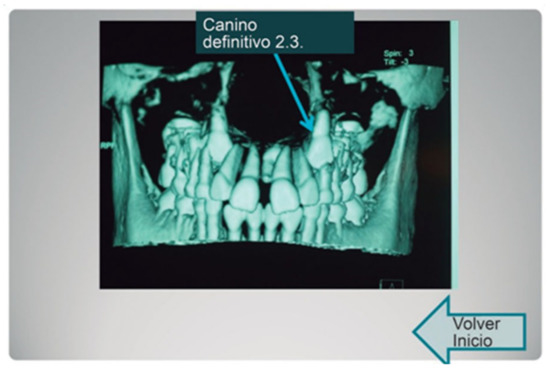

The cases presented were selected because they were the most demonstrative for learning about, and defining, the anatomical structures in the area of the mouth of the growing patient (Figure 1).

In parallel, using the tridimensional images of the jaw, we designed the interactive templates with hyperlinks, so that the student could navigate and choose an option for each assumed clinical scenario, in order to define a more precise diagnosis as a result of identifying anatomical structures (Figure 2).

Figure 1. Example of the CT image chosen for the clinical cases.

Figure 2. Example of 3D image chosen from one of the interactive presentations.